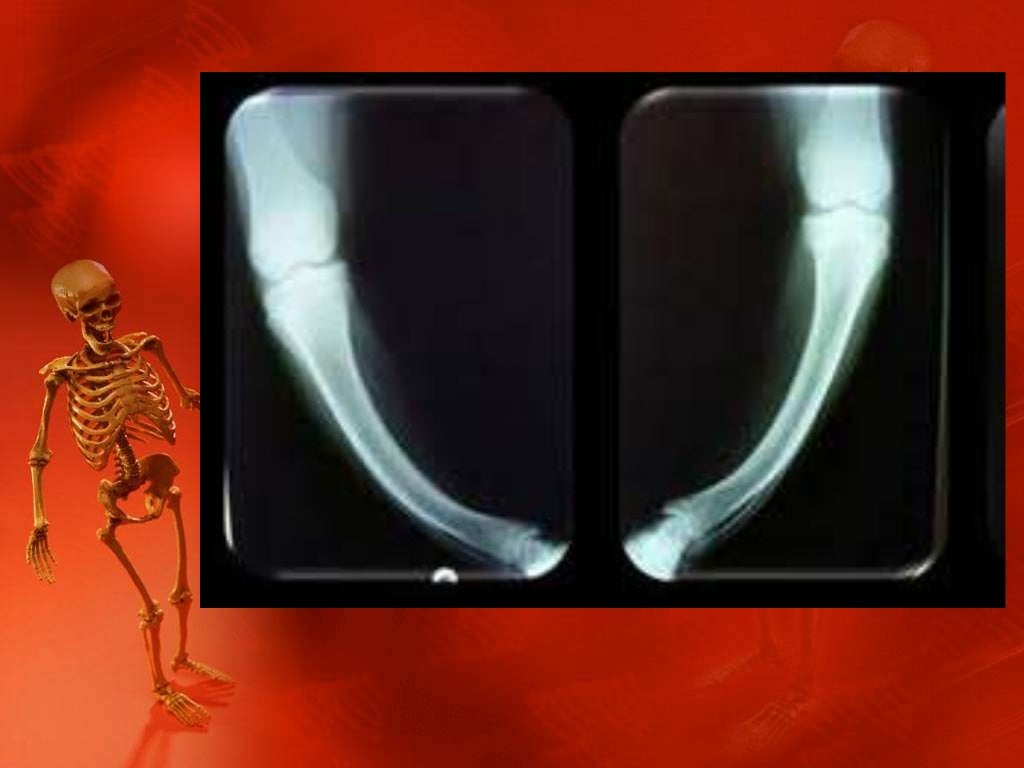

4. Osteogénesis imperfecta. La osteogénesis imperfecta es una enfermedad ósea que aparece a causa de un trastorno genético, el cual es responsable de que los huesos sean mucho más débiles de lo normal. Esto hace que el afectado sufra fracturas con mucha frecuencia, a veces incluso sin traumatismos aparentes.